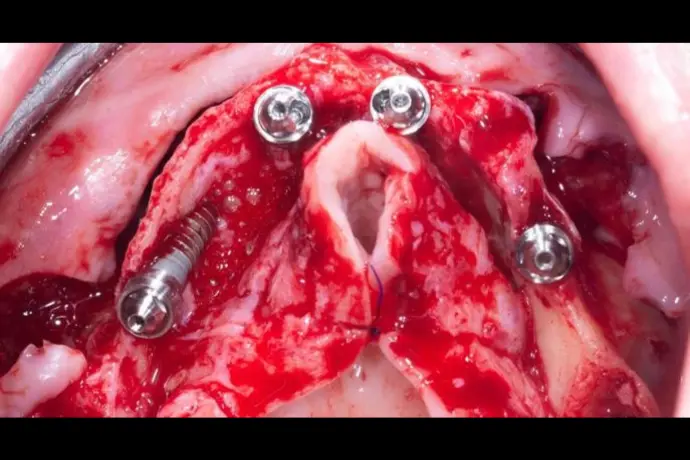

Référentiel Full Arch Club : All-on-4, All-on-X, palatal approach, trans-sinus, pterygoïdes, subpériostés personnalisés. Moins invasif, plus sûr.

Chirurgie et mise en charge immédiate avec une approche sans greffes osseuse et prédictible.

Opération chirurgicale en direct réalisée par le Dr Bernardo Nunes de Sousa